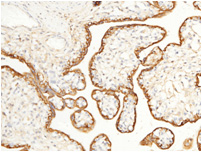

• Human placenta![]() Fig 3. Immunochemical staining of human target E with rabbit mAb. The image showing positive staining of trophoblast. | • Human liver![]() Fig 4. Immunochemical staining of human target E with rabbit mAb. The image showing membrane staining of hepatocyte. |